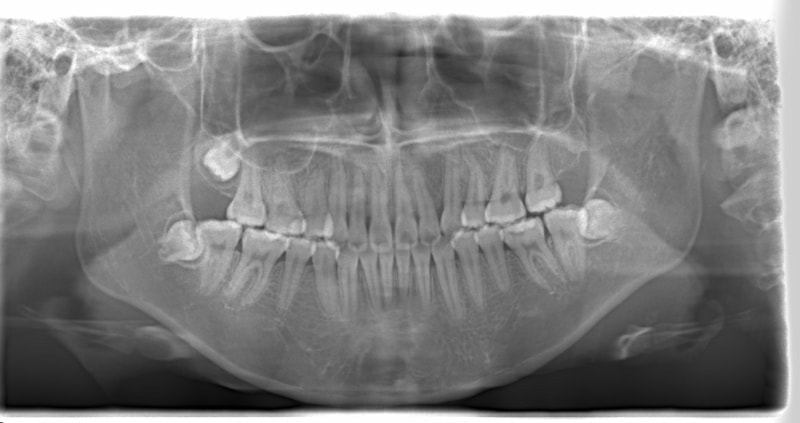

治療開始時